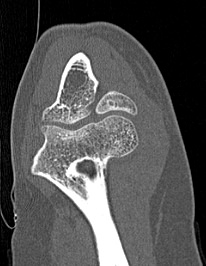

Одним из наиболее информативных методов исследования локтевого сустава является мультиспиральная компьютерная томография. Мультиспиральная КТ локтевого сустава позволяет оценить состояние костных структур и капсульно-связочного аппарата сустава. В отличие от обычного рентгена, при котором изображения накладываются друг на друга, мультиспиральная компьютерная томография с помощью рентгеновских лучей сканирует исследуемую область в разных плоскостях, делая множество тончайших срезов и преобразуя данные в цифровые трехмерные изображения.

Костная ткань хорошо поглощает рентгеновские лучи, поэтому кости ярко визуализируются на снимках КТ. Компьютерная томография в первую очередь востребована в ортопедии и травматологии. Методика широко применяется для диагностики костной патологии. С помощью КТ можно оценить плотность костной ткани и выявить косвенные признаки остеопороза. В случае перелома можно определить точную локализацию костных отломков, что особенно важно при планировании оперативного вмешательства и в послеоперационном периоде для наблюдения за процессом восстановления. КТ также помогает в диагностике различных артритов и артрозов.

- Что покажет КТ локтевого сустава

Что покажет КТ локтевого сустава

- врожденные особенности строения;

- сокращение плотности костей при остеопорозе;

- воспалительные процессы не только в самом суставе, но и в тканях, которые окружают его;

- переломы и трещины костей;

- дегенеративно-дистрофические изменения;

- гнойные процессы;

- инородные тела

- новообразования костей и мягких тканей (не только первичные опухоли, но и метастазы).